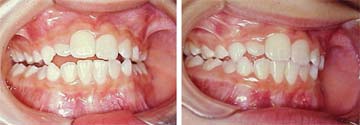

Para concluir este tema apresentaremos, como exemplo, um caso simples de mordida cruzada postural, desencadeada por respiração bucal em decorrência de uma rinite alérgica, a qual foi logo diagnosticada e convenientemente tratada. Observaremos também as prováveis implicações nas articulações temporomandibulares, estimuladas pelo uso do hiperbolóide com intuito de reprogramar o sistema estomatognático.

Fig. 1 |

Com apenas seis meses de tratamento, a harmonia facial é restabelecida e o desvio postural da mandíbula deixa de influenciar a face da paciente. |